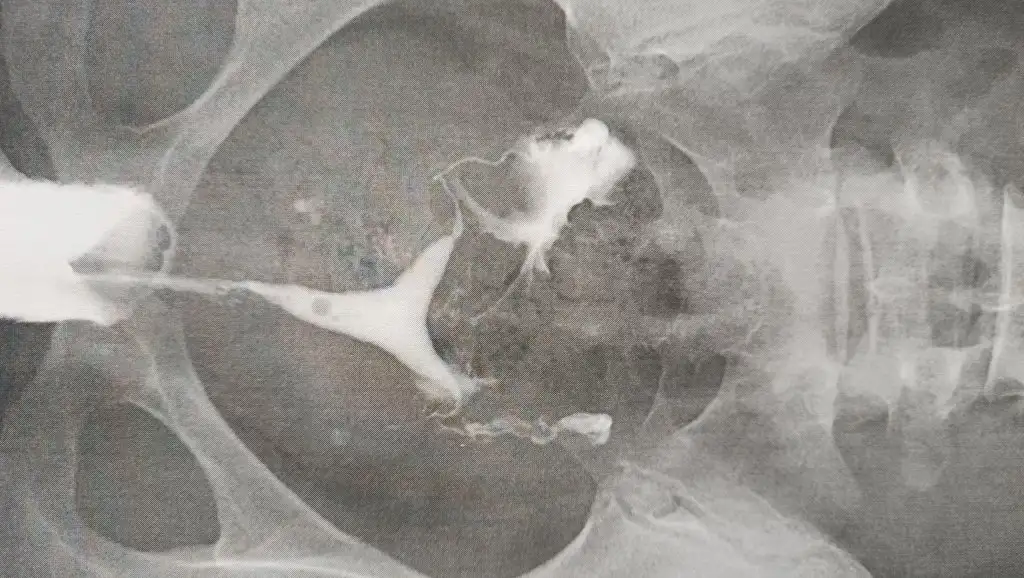

Rahim filminde baya basınçlı vermiş sanırım altta görsel ekledim ama raporda geçiş olmadı yazılmışRahim filmi sırasında açarlar tıkalı tüpü bnde aynı şeyi yaşadım tuplerimi açtılar yumurtlaliklarda tembellikte varsa sayım yapıp catlatirlar veya eşinde sperm sorunu varsa takipli hamile kalırsın